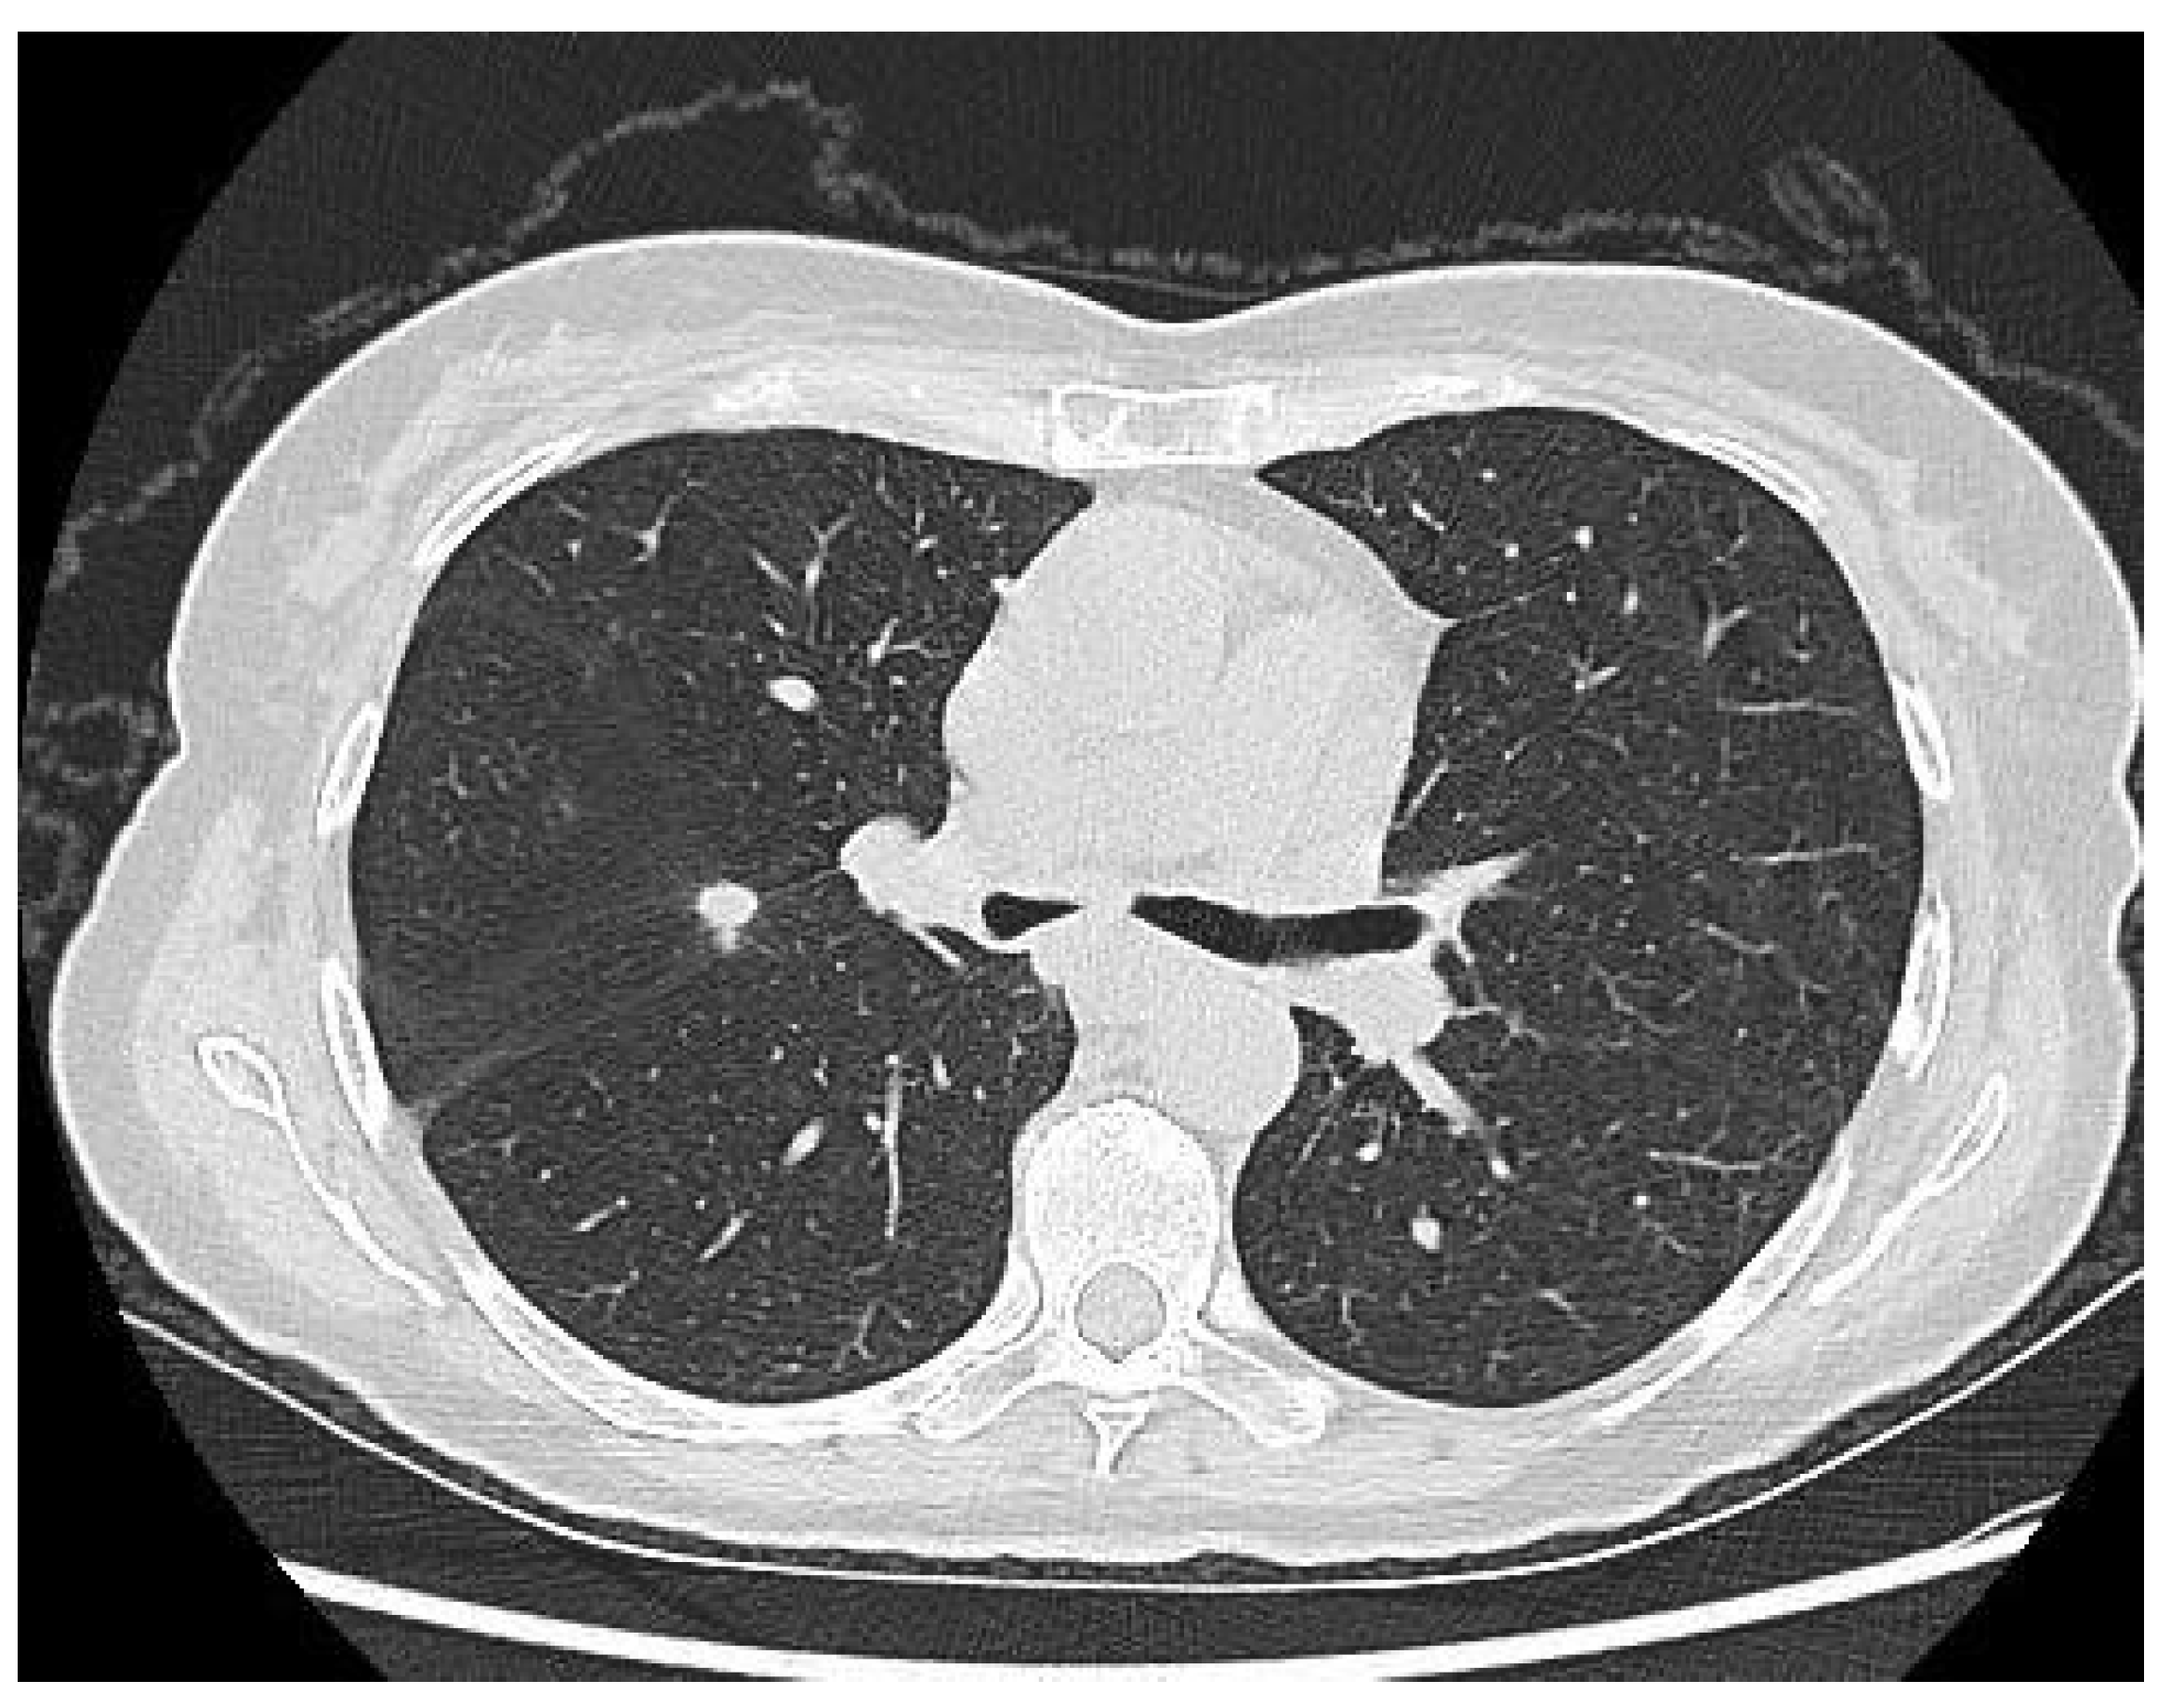

Krukenberg Tumor in Association with Ureteral Stenosis Due to Peritoneal Carcinomatosis from Pulmonary Adenocarcinoma: A Case Report

2. Case Report